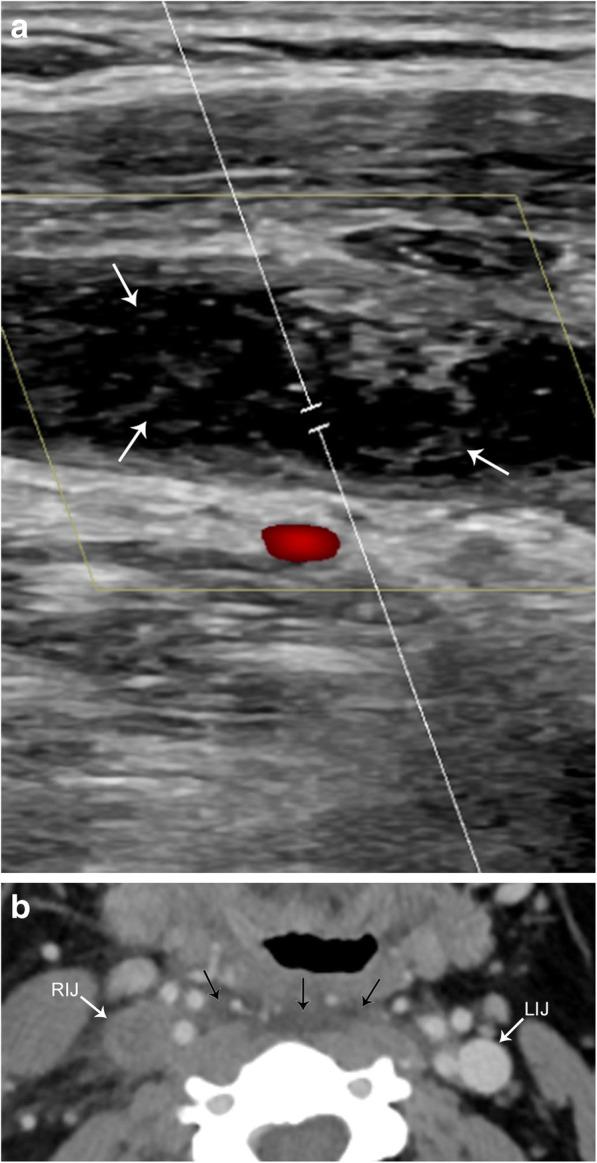

The complex anatomy of the carotid space within a small confined area is unique to the head and neck and allows for a vast array of pathology. This paper will review the anatomy of the carotid space from the skull base to the thorax, defining its borders at multiple levels, as well as its contents. The paper will also describe the myriad of mass lesions and vascular pathologies that may occur within the carotid space. The discussion will include anatomic considerations in differential diagnoses, imaging features, and lesion characteristics across multiple imaging modalities including CT, MRI, ultrasound, and conventional angiography. Entities discussed include paragangliomas, nerve sheath tumors, meningioma, fibromuscular dysplasia, carotidynia, thrombus, dissection, pseudoaneurysm, and pathology of the deep cervical chain lymph nodes. Understanding the complex and unique anatomy of the carotid space, as well as the nuances of navigating a broad differential, will empower the reader to make an accurate diagnosis.

在狭小受限区域内,颈动脉间隙复杂的解剖结构是头颈部所特有的,且会引发大量病变。本文将回顾从颅底到胸部的颈动脉间隙解剖结构,界定其在多个层面的边界及其内容物。本文还将描述可能出现在颈动脉间隙内的众多肿块性病变和血管病变。讨论将包括鉴别诊断中的解剖学考量、多种成像方式(包括CT、MRI、超声和传统血管造影)的成像特征及病变特点。所讨论的疾病包括副神经节瘤、神经鞘瘤、脑膜瘤、纤维肌发育不良、颈动脉痛、血栓、夹层、假性动脉瘤以及颈深链淋巴结病变。了解颈动脉间隙复杂独特的解剖结构以及鉴别广泛病变的细微差别,将使读者能够做出准确诊断。